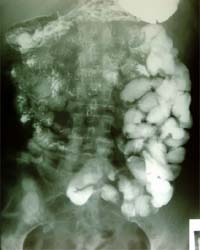

6.経口小腸造影 & 経口小腸二重造影 最初にバリウムを飲んで頂きます。透視台の上で体位を変えながら、バリウムを小腸と大腸の吻合部まですすめます。体位は、頻繁に変えません。流れを見ながら時間をおいて(10分〜20分)仰向けや横向きになって頂きます。この間に、おなかを押さえたりして小腸の狭窄や病変がないか見ていきます。大腸まで到達したら、発泡剤を飲んでもらって小腸をふくらまし全体の写真を撮っていきます。この検査にかかる時間は個人差があります。流れの速い患者さまは30分〜1時間、遅い患者さまは2時間〜3時間かかる場合があります。 |